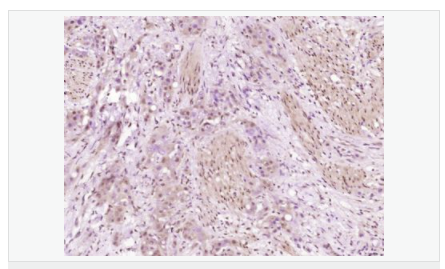

| 產(chǎn)品應用 | WB=1:500-2000 ELISA=1:5000-10000 IHC-P=1:100-500 IHC-F=1:100-500 ICC=1:100-500 IF=1:100-500 (石蠟切片需做抗原修復) not yet tested in other applications. optimal dilutions/concentrations should be determined by the end user. |

| 產(chǎn)品介紹 | Increase in fetal surfactant synthesis and lung maturity is caused by the glucocorticoidal induction of enzymes required for phosphatidylcholine synthesis towards the end of gestation (1). The regulation of gestational age-dependent induction of phosphatidylcholine synthesis by glucocorticoids is still unclear (1). The rate-controlling enzyme in the phosphatidylcholine biosynthetic pathway is CTP-phosphocholine cytidylyltransferase A (CCT A) (2–4). In cultured eukaryotic cells, this enzyme is essential for survival (3). The alpha isoform is located in the nucleus and is regulated by reversible phosphorylation and membrane association (3). There is significant identity between the alpha-helical membrane-binding domains of CCT A and soybean oleosin (2). Expressed CCT A has lipid-dependent cytidylyltransferase activity (5). The gene which encodes CCT A maps to human chromosome 3q (4). Function: Controls phosphatidylcholine synthesis. Subunit: Homodimer. Subcellular Location: Cytoplasm; cytosol. Membrane. It can interconvert between an inactive cytosolic form and an active membrane-bound form. Post-translational modifications: The serine residues of the C-terminus are phosphorylated. The inactive soluble form is stabilized by phosphorylation, the active membrane bound form is promoted by anionic lipids or diacylglycerol, and is stabilized by dephosphorylation. Similarity: Belongs to the cytidylyltransferase family. SWISS: P49585 Gene ID: 5130 Database links: Entrez Gene: 5130 Human Entrez Gene: 13026 Mouse Omim: 123695 Human SwissProt: P49585 Human SwissProt: P49586 Mouse Unigene: 135997 Human Unigene: 98775 Mouse Important Note: This product as supplied is intended for research use only, not for use in human, therapeutic or diagnostic applications. |